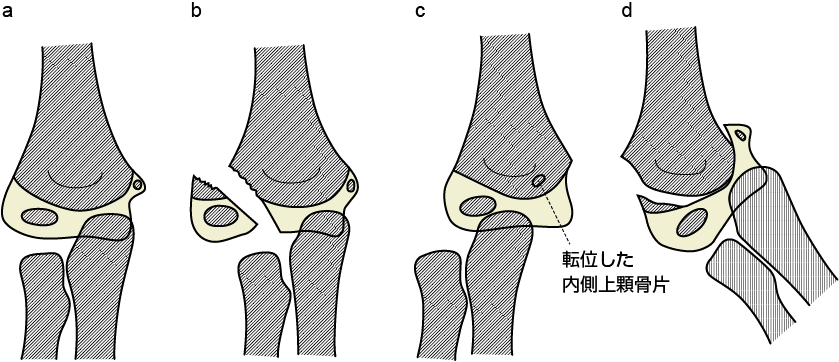

他の損傷との鑑別点

a.正常

b.上腕骨外側顆骨折(外側顆は外側に移動し、橈骨の長軸の延長

が外側顆の中心を通らない)

c.肘関節脱臼(外側顆の位置は骨幹端部に対して正常で、橈骨長軸

の延長が外側顆中心を通らない)

d.骨端離開

出典

img

1: 井上博:小児四肢骨折治療の実際 改訂第2版. 金原出版, 2001:87